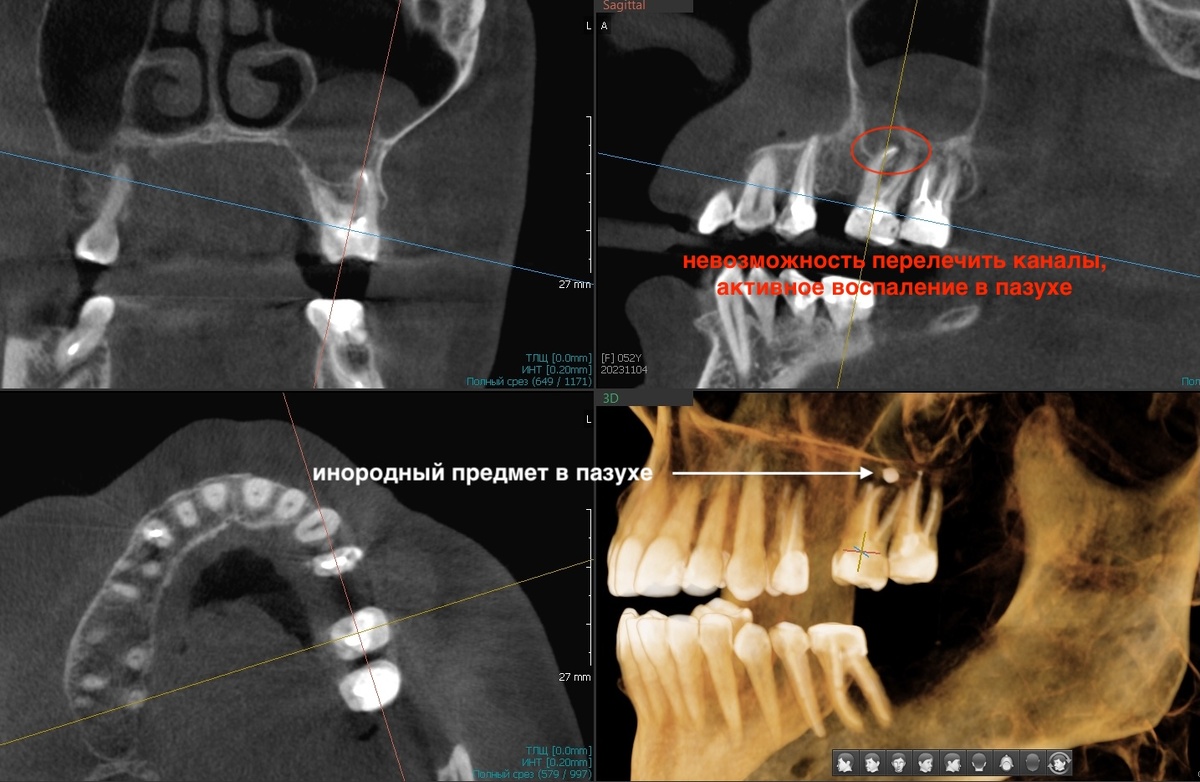

В области удалённого 2.6 ситуация тоже дефицитная. Кости не хватает по высоте - до гайморовой пазухи слишком малое расстояние. А в самой пазухе на КТ видно инородное тело и присутствует.

-4

Скорее всего, пломбировочный материал от предыдущего неудачного лечения. Кто-то переусердствовал с пломбированием каналов и вывел материал в пазуху, а это чревато микозом (грибы любят инородные предметы в пазухах особенно). Отправили пациентку к ЛОР-врачу. Нельзя делать синус-лифтинг с инородным телом в пазухе.

Ждали заживления. Потом синус-лифтинг - поднятие дна пазухи с подсадкой кости. Ещё ждали. Кость должна созреть, стать плотной. Только потом можно ставить имплантат.